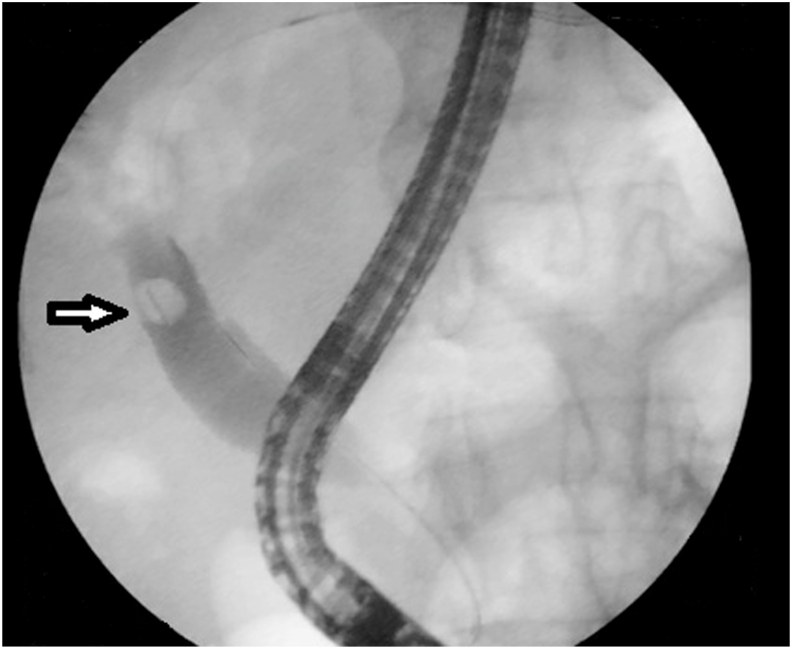

An 83-year-old man, known case of diabetes mellitus taking insulin, presented with severe abdominal pain, nausea, and jaundice for 3 days. Past surgical history included uneventful laparoscopic cholecystectomy for cholelithiasis 8 years back, with intraoperative cholangiogram showing clear bile ducts. The patient has episodic right upper quadrant abdominal pain for the past six months. The abdominal pain lasted for less than 6 hours without jaundice or fever. However, he has developed jaundice since three days. On physical examination, he was febrile (temperature of 38.5 °Celsius), had tachycardia, icterus, and tenderness in the right upper quadrant. Laboratory investigations revealed leucocytosis and elevated liver enzymes: alanine aminotransferase (ALT)260 U/L (N 7–40), aspartate aminotransferase (AST) 240 U/L (N 7–40), gamma-glutamyl transferase (GGT) 330 U/L (N 7–32) and a total bilirubin level of 102 μmol/L (N 5.1–17) with a direct bilirubin level of 91 μmol/L. Contrast-enhanced computed tomography of the abdomen (CT) showed intra and extrahepatic ducts dilatation secondary to a hyperdense object located in the distal common bile duct (CBD) as shown in Fig. 1. Based on clinical symptoms, laboratory results, and tomography findings, the diagnosis of cholangitis was confirmed. Broad-spectrum antibiotics and fluid resuscitation were started immediately and an urgent endoscopic retrograde cholangiopancreatography (ERCP) was performed. The ERCP revealed intra and extra ductal dilatation secondary to an occluding stone in the CBD formed around the surgical clip (Fig. 2). An endoscopic sphincterotomy was performed and the clip was removed. The patient was discharged after 6 days of hospitalization. At the last follow-up of one year after his admission, the patient is symptom-free with normal liver enzymes and abdominal CT.